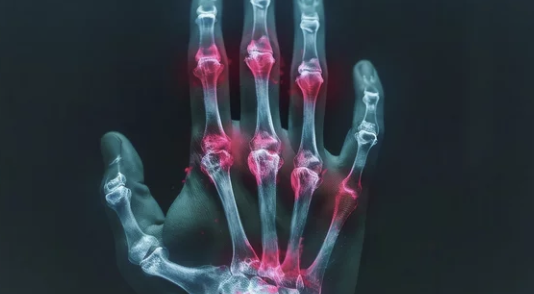

손가락 관절염은 손가락의 관절에 염증이 생기며 통증, 부종, 움직임 제한 등이 발생하는 질환으로, 주로 두 가지 유형으로 나뉩니다:

- 골관절염(퇴행성 관절염): 관절의 연골이 점차 닳아 없어지며 발생.

- 류마티스 관절염: 면역 체계 이상으로 관절에 염증이 생기고 손가락이 변형될 가능성이 높습니다.

- 관절 부위가 붓고 열감이 느껴진다.

- 관절이 변형되고, 움직임이 제한된다.